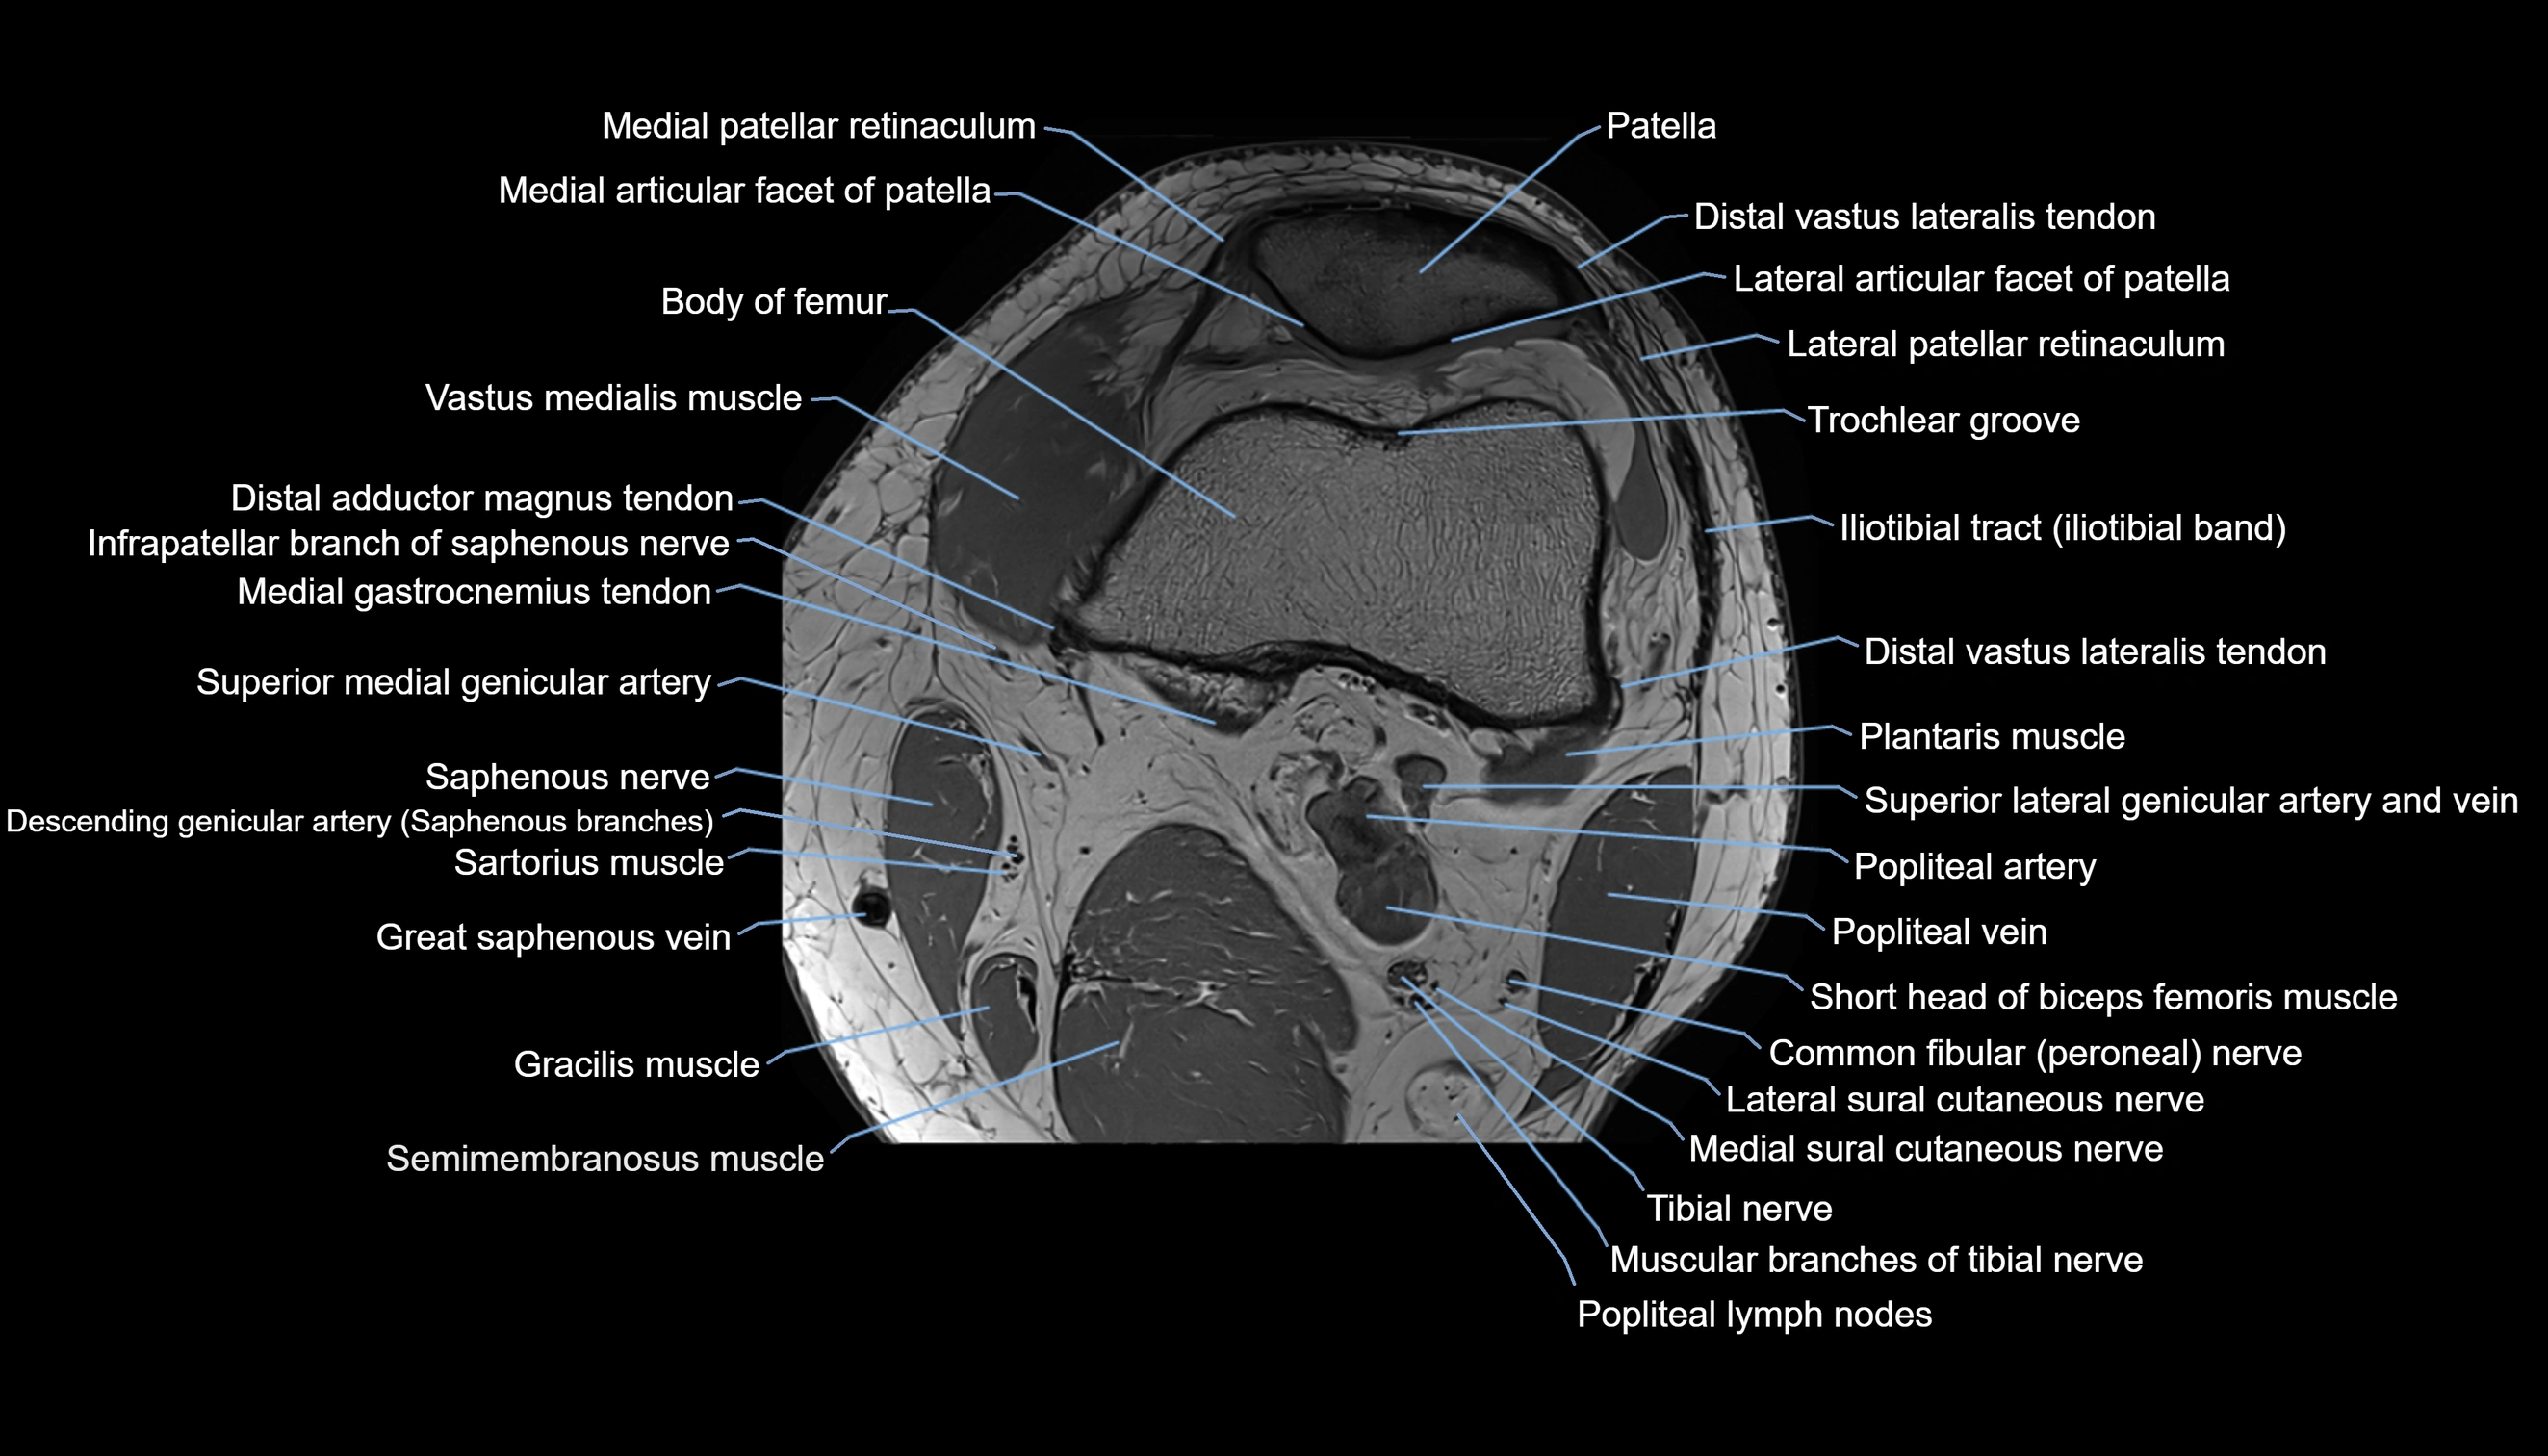

- Knee Joint

- Patella

- Popliteal artery

- Popliteal lymph nodes

- Popliteal vein

- Tibial nerve

- Vastus medialis muscle

- great saphenous vein